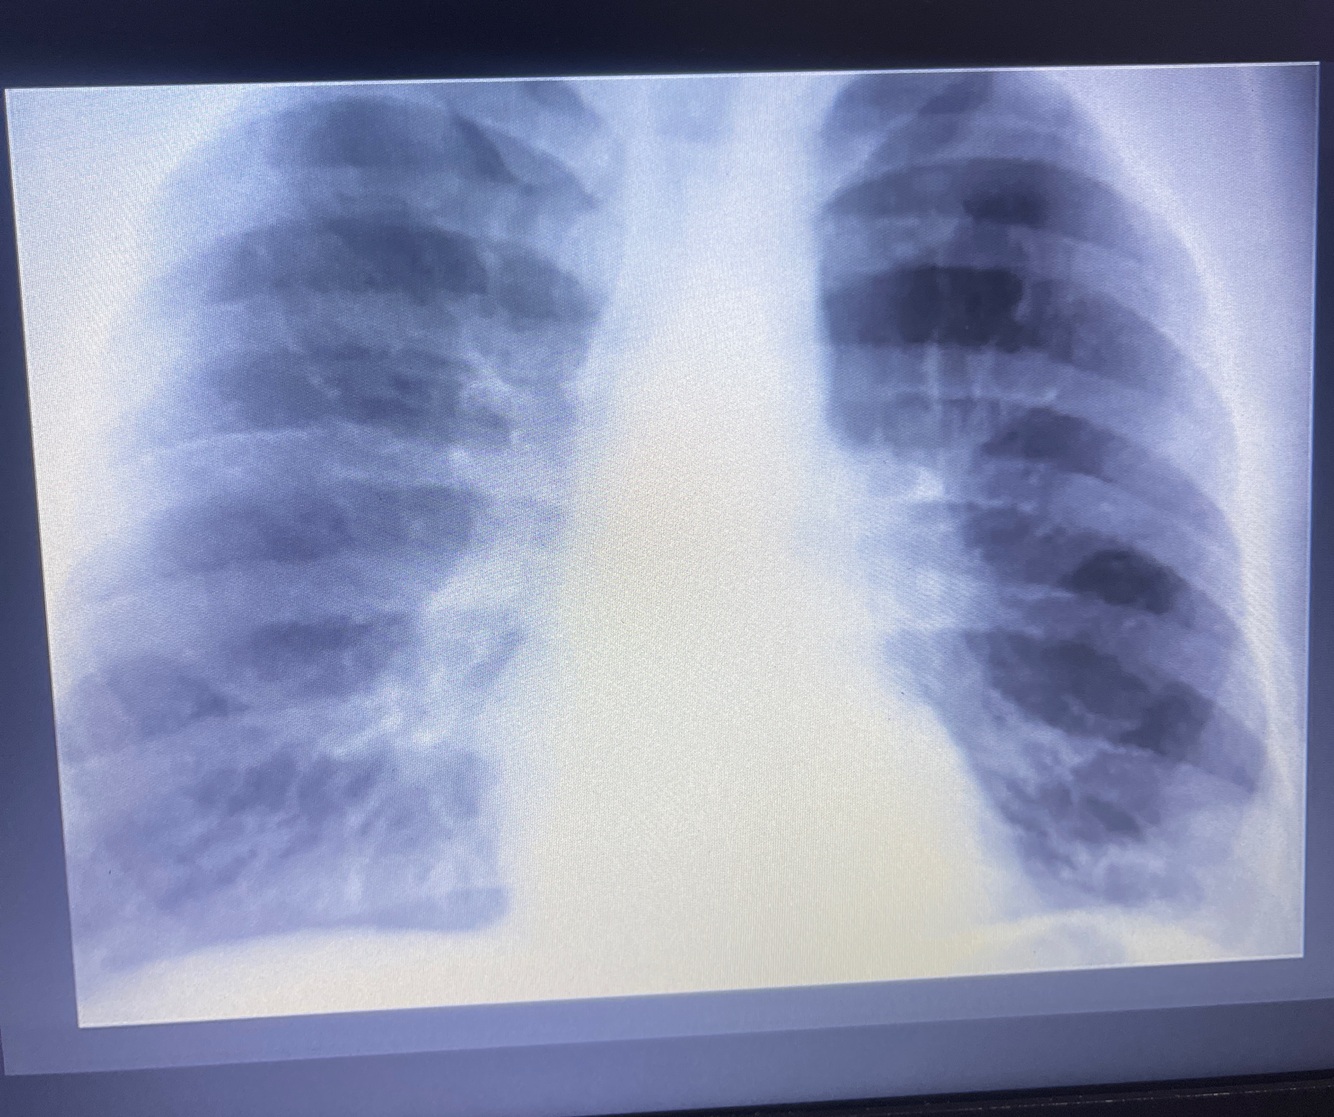

Rx de Tórax

Sinal de WESTERMAK

Diminuição da trama vascular, oligoemia ou seja hipodensidade focal, geralmente é triangular

Corcova de Hampton

Ela geralmente é hiperdensa, sugestiva de infarto pulmonar